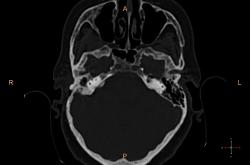

Справа в полости среднего уха небольшое количество жидкости? Пирамида и сосцевидный отросток склерозированы. У нас направляют на КТ только при подозрении на деструкцию или опухоль. Исследование выполняются на специальной программе для височных костей , срезы по 0.1 или 0.05 см, костная структура видна изумительно. А чаще изменения височных костей обнаруживаются как случайная находка при КТ черепа (хорошо видно на "сердечном" режиме).

У нас минимальный срез идет по 0,75мм, мне кажется если есть возможность провести КТ-исследование, следует это делать, что косается данной пациентки, все не так просто, у неё имеется клинически свищ с отделяемым, позади ушной раковины, где имеено и откуда идет свищ четко видно, а так все верно имеется эпитимпанит и антрит.

Согласен, ///если есть возможность провести КТ-исследование, следует это делать///, с Шуллерами-Майерами не сравнить. Кстати, состояние аттико-антральной области обычно более демонстративно на аксиальных срезах уровня латерального полукружного канала.

Касаюсь Андрей Юрьевич, лобарант меня позвал в плане выбора протокола исследования, а я при наложении плоскости сканирование на топограмме, взял и не учел оптико-меатальную линию, получилось несколько неуклюже, поэтому только на станции подорвался выравнивать её при анализе сканов :-(

Свищевой ход.